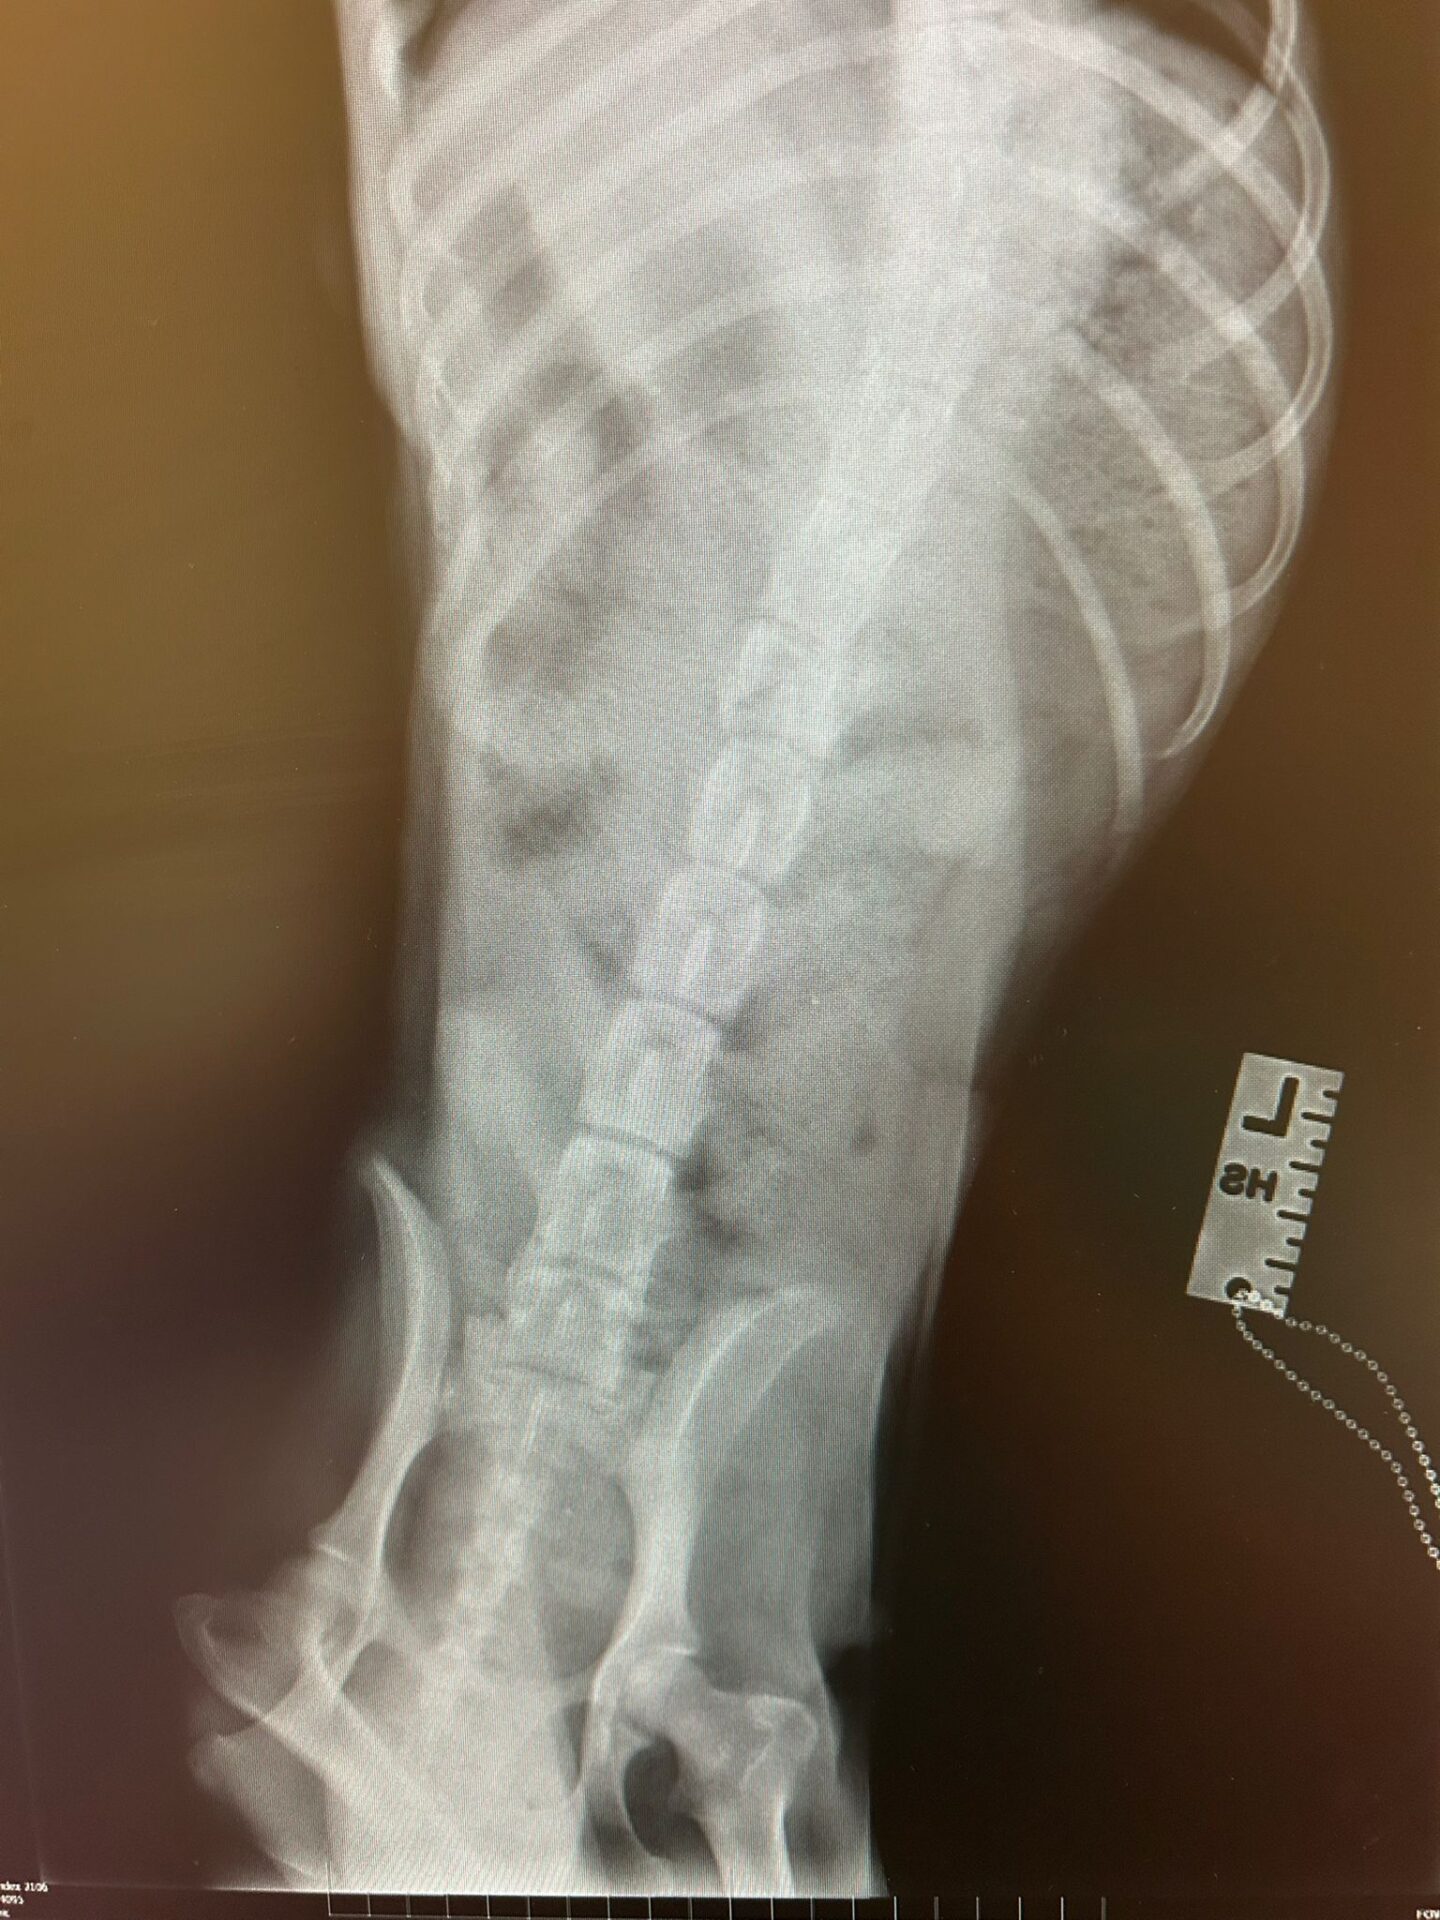

Pia konnte ihre Hinterbeine nicht bewegen und hatte eine alte Verletzung an der Wirbelsäule. Halb gelähmt muss sie ihre Welpen auf die Welt gebracht haben und niemand hat Pia geholfen.